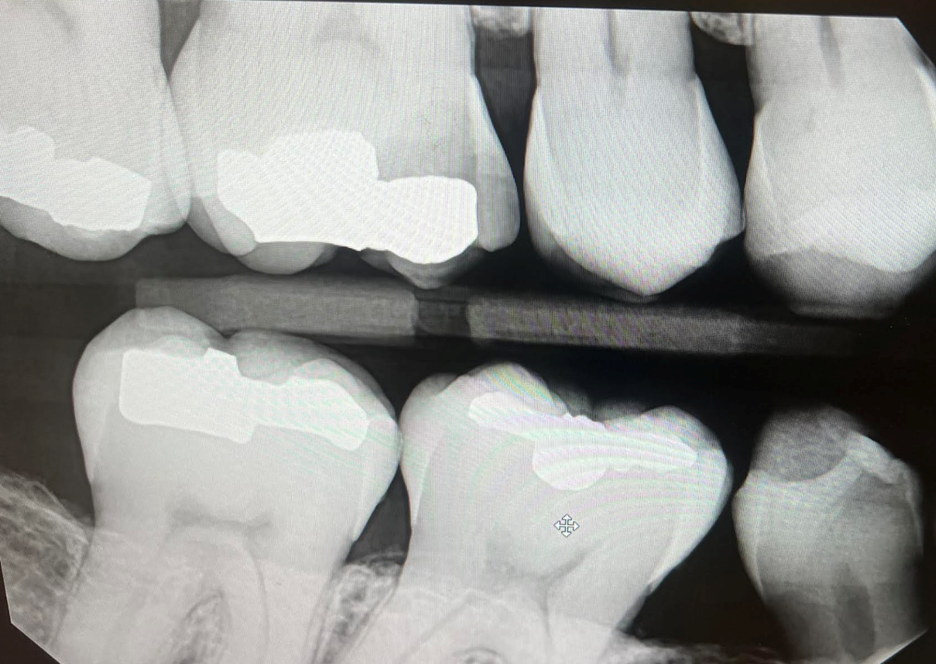

Example 1, Eliminating a “judgement call”

- If you are like our practice, you see a lot of examples of a tooth that could potentially either qualify for a large filling or a crown. This can be challenging as we are always trying to be as conservative as possible while providing the best standard of care. This can also be challenging for our front staff in dealing with insurance denials as well. In this example tooth #3 has recurrent decay under an existing large amalgam restoration: